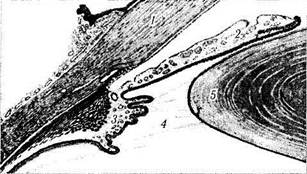

Рис. 3.4.2. Соотношение структур переднего отдела глаза (схема) (по Rohen; I979):

а — срез, проходящий через структуры переднего отдела глаза (/ — роговая оболочка; 2 — радужная оболочка; 3 — ресничное тело; 4 — ресничный поясок (циннова связка); 5 — хрусталик); б — сканирующая электронная микроскопия структур переднего отдела глаза (/ — волокна зонулярного аппарата; 2 — ресничные отростки; 3 — ресничное тело; 4 — хрусталик; 5 — радужка; 6 — склера; 7 — шлеммов канал; 8 — угол передней камеры)